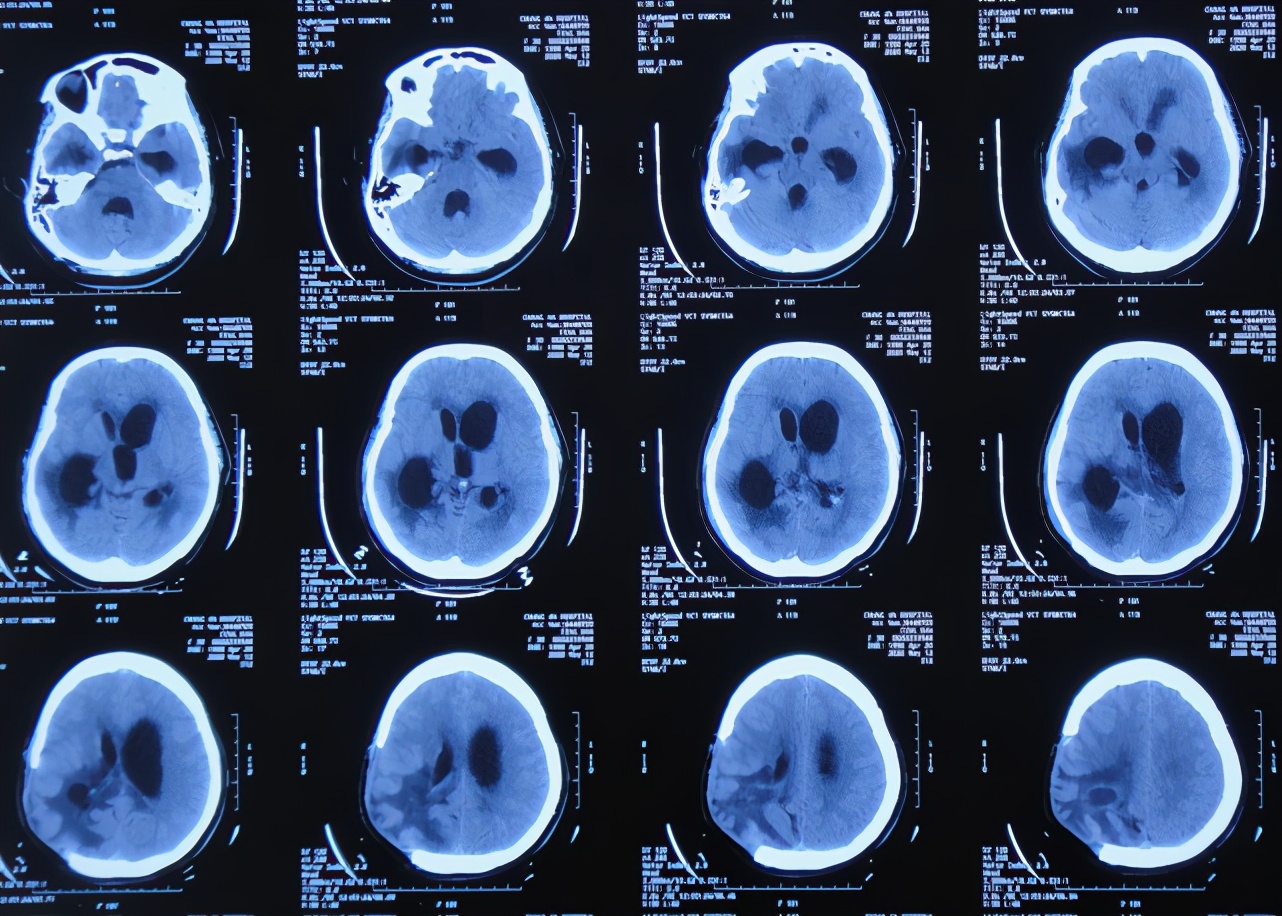

入院当天复查头颅CT示脑血管畸形术后改变,脑积水引流术后,脑膨出,右侧颞枕顶叶及左侧额叶脑水肿,严重脑室粘连( 图-17 );胸部CT示双肺肺炎(片子丢失)。

图-17: 2020年7月5日头颅CT

入院次日即2020年7月6日,进行了颞角外引流术,术后当天复查头颅CT示脑室内有2根管( 图-18 ), 脑脊液细菌培养示肺炎克雷伯菌(仍是外院开颅术后14天时查出的细菌,说明之前的细菌一直并未彻底消灭)。

图-18: 2020年7月6日头颅CT